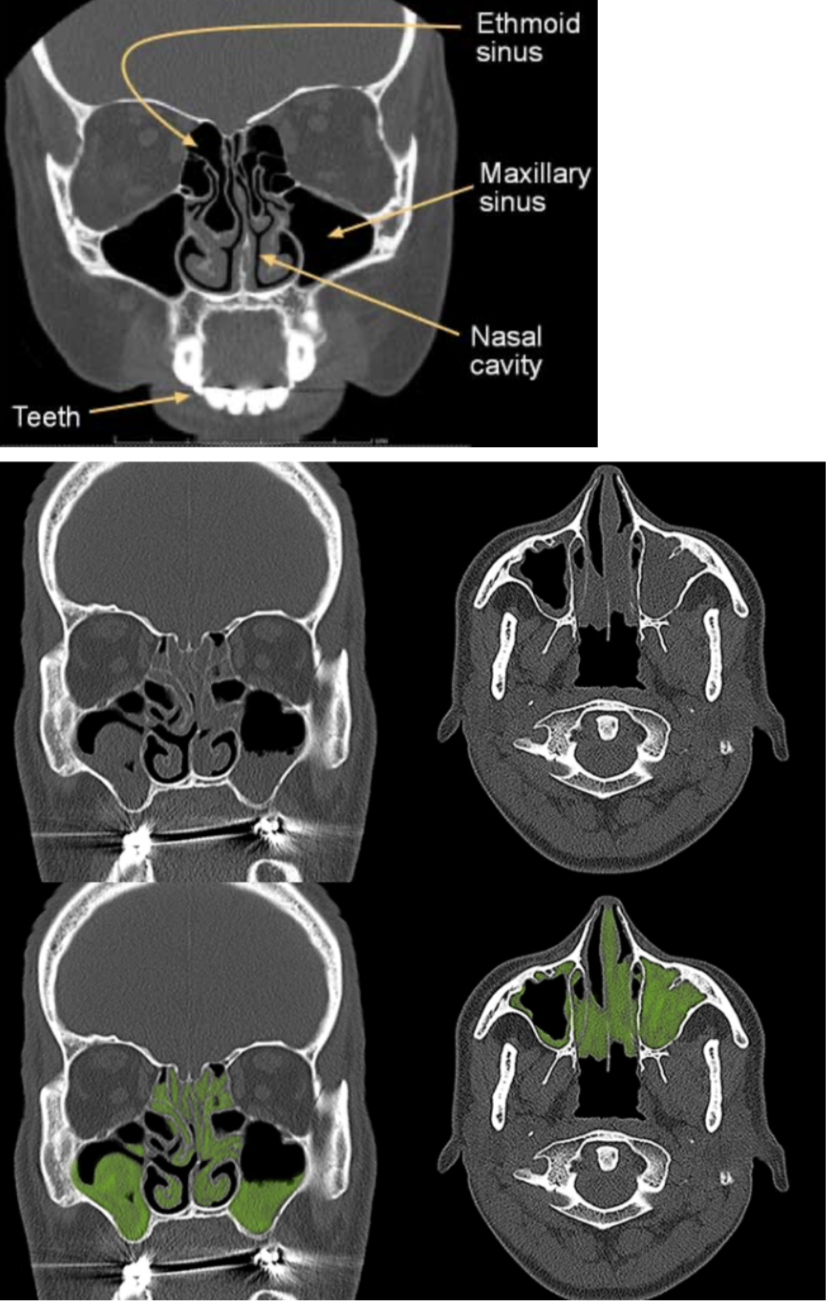

Estudio de imagen que se solicita para sinusitis (Gold standard)

Tomografía de senos paranasales y nariz

Indicaciones de TC de senos paranasales en sinusitis: (3)

(Se solicita principalmente en pacientes con mayor riesgo o enfermedad complicada)

A

Oncológicos (riesgo de complicaciones o infecciones oportunistas.)

Inmunosuprimidos (riesgo de infecciones graves o atípicas.)

Sinusitis crónica (evaluar la extensión, anatomía y posibles complicaciones.)

Dx

Sinusitis

31

32